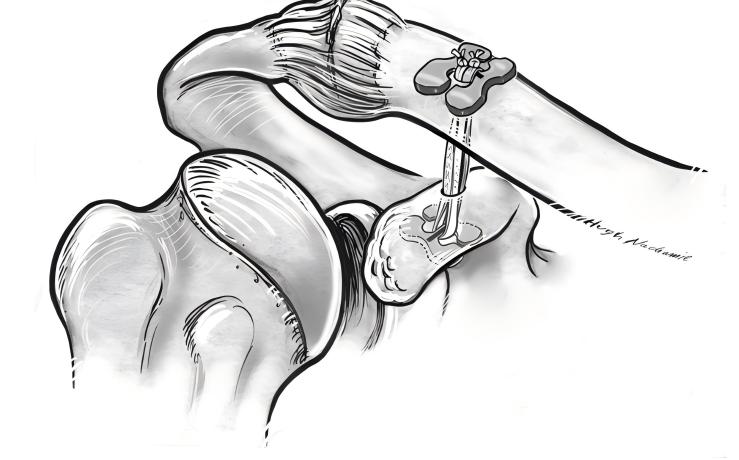

Если вам необходимо усовершенствованное лечение вывихов суставов переменного тока, восстановление титановых пластин предлагает надежное решение. Хирурги используют пошаговый подход для восстановления стабильности и функции вашего плеча. Вот что вы можете ожидать во время процедуры:

Вам сделают общий наркоз, чтобы вы чувствовали себя комфортно.

Хирургическая бригада укладывает вас в положение шезлонга. Ваши плечи становятся мягкими, а голова наклоняется в здоровую сторону.

Хирург обнажает поверхность клювовидного отростка и конец ключицы.

Аппарат рентгеноскопии помогает бригаде четко видеть вашу ключицу.

Хирург делает разрез кожи длиной 4–5 см у внутреннего края акромиально-ключичного сустава.

Кожу и ткани вскрывают, чтобы добраться до вывихнутого сустава.

Порванную ткань удаляют. По латеральному краю клювовидного отростка вводят сосудистый зажим.

Хирург создает туннель и отмечает внешний конец ключицы.

Направитель вводится в нижний край клювовидного отростка по туннелю у отметки ключицы.

Положение направляющей подтверждается с помощью рентгеноскопии С-дуги.

Совет: при ремонте титановых пластин часто используются конструкции без узлов и проволочная лента с сердечником для фиксации соединения. Этот метод снижает риск проскальзывания узла и повышает долговременную стабильность.

Вы получаете выгоду от техники, которая фокусируется на точном размещении и сильной фиксации. Использование титановых устройств помогает заживлению сустава в правильном положении и способствует раннему движению.